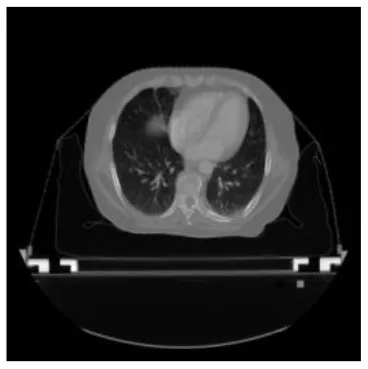

According to the acquired model parameters mentioned above, the testing set was calculated and examined. The performance of the modified algorithm for automatic organ segmentation in CT images is shown in Table 1. The organ contours segmented automatically by the algorithm were similar to those delineated by physicians manually. The model parameters including DSC, Accuracy, Recall, and Precision evaluation ones were served to evaluate the segmentation effectiveness of each organ in the validation and testing sets. In our work, the BCDU-Net CNN algorithm model was used to automatically segment different organs with the different training parameters such as epoch learning rate. The CT images which were randomly selected from the patients were put into the network model for training, and then the contours of different organs which were delineated automatically by the AI technology and manually by medical doctors were evaluated with the similarity coefficients, respectively. The results are given in Table 2. Most of the DSC values were better than 0.85 and among them the best even reached up to 0.9676. Generally, the automatic segmentation results met the requirements of clinical practice.

| Input CT image | Organs with manual segmentation | Organ with automatic segmentation | |

| Bladder | ![]() | ![]() | ![]() |

| Brainstem | ![]() | ![]() | ![]() |

| Eye-L | ![]() | ![]() | ![]() |

| Eye-R | ![]() | ![]() | ![]() |

| Femur-L | ![]() | ![]() | ![]() |

| Femur-R | ![]() | ![]() | ![]() |

| Heart | ![]() | ![]() | ![]() |

| Intestine | ![]() | ![]() | ![]() |

| Kidney-L | ![]() | ![]() | ![]() |

| Kidney-R | ![]() | ![]() | ![]() |

| Liver | ![]() | ![]() | ![]() |

| Lung-L | ![]() | ![]() | ![]() |

| Lung-R | ![]() | ![]() | ![]() |

| Mandible | ![]() | ![]() | ![]() |

| Rectum | ![]() | ![]() | ![]() |

| Spleen | ![]() | ![]() | ![]() |

| Stomach | ![]() | ![]() | ![]() |

The result of manual and automatic organ segmentation.